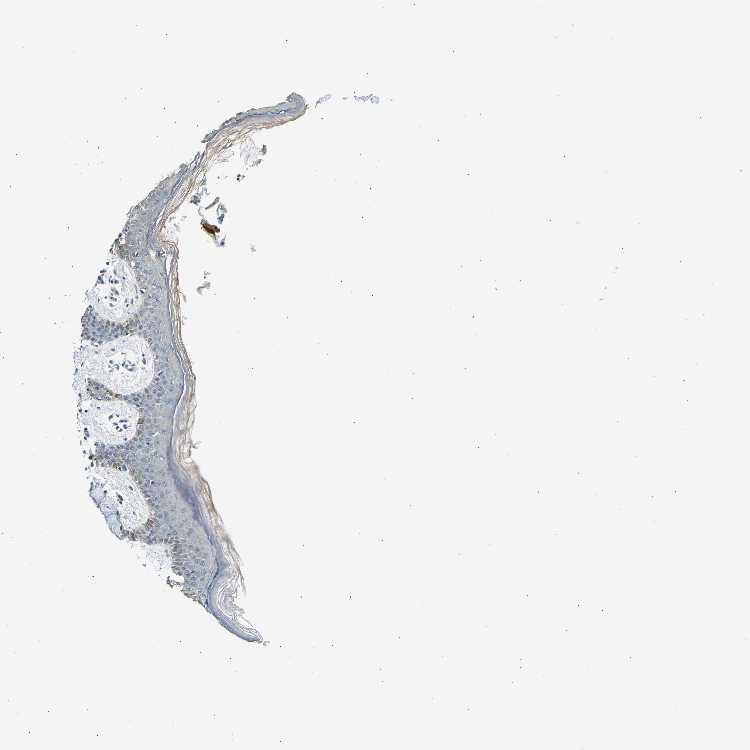

SKIN 1 - Antibody stainingi

Antibody staining in the annotated cell types in the current human tissue is reported as not detected, low, medium, or high, based on conventional immunohistochemistry profiling in selected tissues. This score is based on the combination of the staining intensity and fraction of stained cells.

Each image is clickable and will lead to virtual microscopy that enables deeper exploration of all samples and also displays staining intensity scores, fraction scores and subcellular localization as well as patient and tissue information for each sample.

Antibody HPA013407

Langerhans Not detected

Fibroblasts Low

Keratinocytes Low

Melanocytes Medium